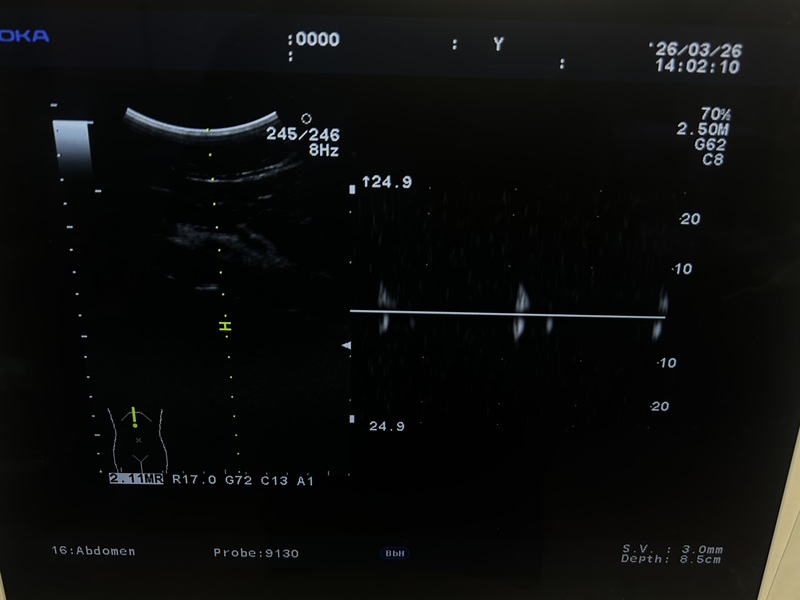

Ultrasound System

Ultrasound